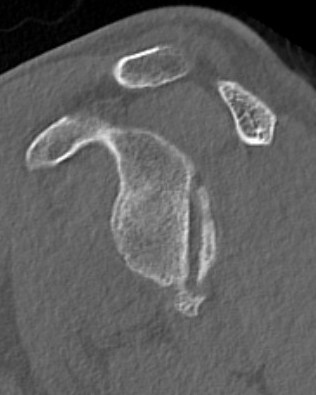

CT scan

Confirms dislocation

Reverse Hill Sachs

Humeral head defect

- caused by impaction of anterior humeral head on posterior glenoid

- intra-articular

- measured as a percentage of the articular surface

Lesser tuberosity fractures

Posterior glenoid fractures / bony bankart